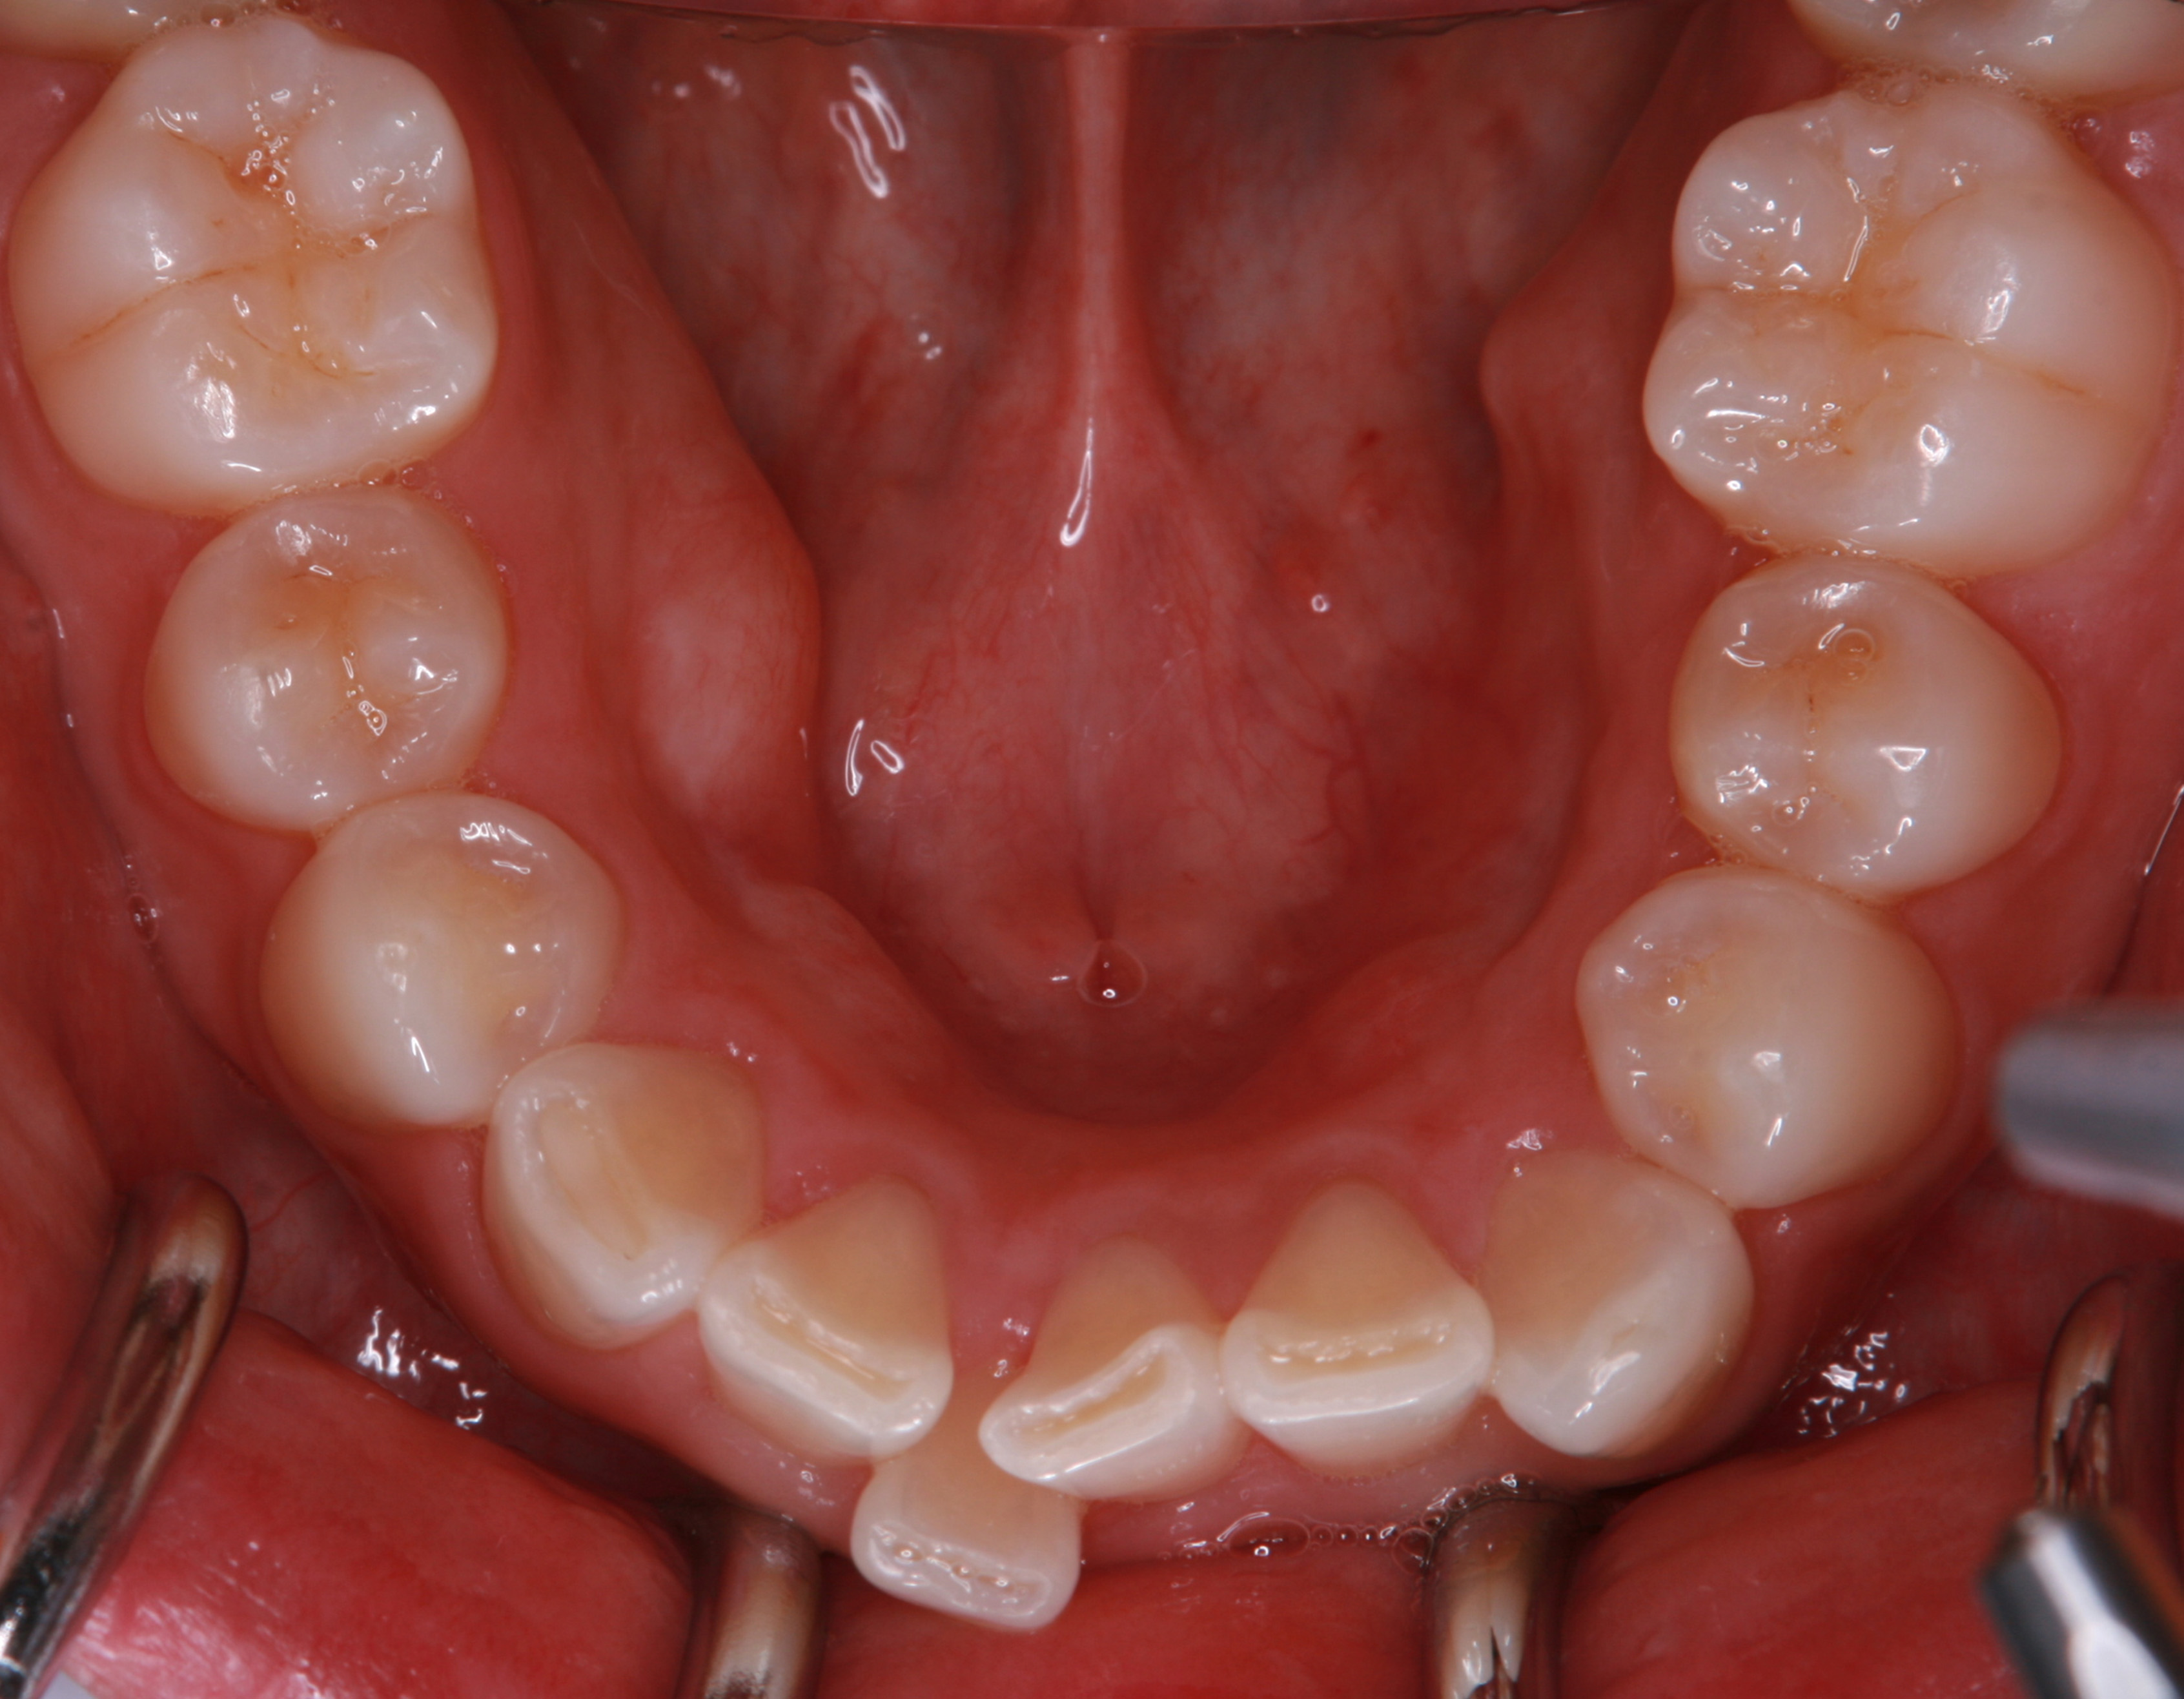

上顎前歯部の部分矯正

術前・術後の比較

治療の経過を表示する

-

患者の方は親知らずの痛みがあり当院にお越しになりました。幼少期から歯医者が苦手で、痛みがあってもなかなか行く勇気がでなかったそうです。笑気鎮静法を併用しながら、右下の親知らずを抜歯しました。

2024.6.25パノラマレントゲン写真

親知らずの痛みがなくなった患者さんは、昔から歯並びが気になっていることを打ち明けてくれました。特に上の歯が少し前に出ていたり、隙間があったりしている点を治したいそうです。そこで、まず上の歯並びの矯正治療を開始しました。

最初のお口の中 ワイヤー装着して治療を開始

治療開始後3ヵ月経過すると、前歯の隙間や全体の乱れが減ってきました。口笛が吹けるようになったとのことです。

最初のお口の中 治療開始3ヵ月後

6ヵ月経過すると、矯正治療を終了し、前歯に被せ物の治療を行いました。

最初のお口の中 2025/3/22

被せ物装着

当院では、歯並びが気になる人に対して、矯正治療を行っています。また今回の症例のようにワイヤーを用いた治療からマウスピース矯正治療も行っておりますので、スタッフにお声かけください。

治療の概要

| 患者属性 | 30代男性、歯科恐怖症 |

|---|---|

| 主訴 | 上の前歯の歯並びを整えたい |

| 診断 | 歯列不正、う蝕歯 |

| 矯正装置 | 矯正ブラケットとワイヤー |

| 治療期間 | 約6ヵ月 |

| 通院回数 | 8回 |

| 治療費 | 矯正:基本料金(220,000円)+調整料(5,500円×6回)、補綴治療:72,600円、費用は税込 |

| 治療内容 | 上顎側切歯を2本抜歯した後、上顎の歯にブラケットを装着し、ワイヤー、矯正用ゴムで歯の移動を行いました。その後、被せ物の治療を行って治療を終了しています。 |

| リスクと副作用 | 矯正治療

補綴治療

|